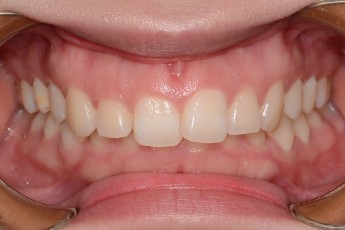

BEFORE & AFTER

- 과개교합교정